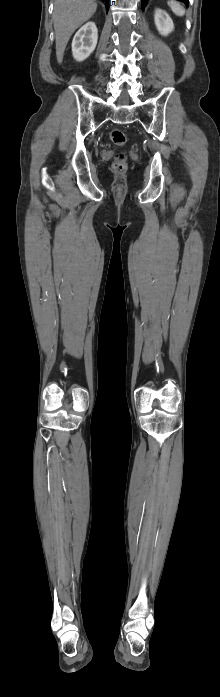

Назад КТ брюшного отдела аорты и сосудов (артерий) нижних конечностей

Основные показания для проведения КТ брюшного отдела аорты и артерий нижних конечностей могут включать:

• Аневризмы: оценка и диагностика аневризм брюшной аорты.

• Стенозы и окклюзии: выявление и оценка степени сужения или блокировки артерий.

• Тромбозы: обнаружение тромбов и оценка их размера и локализации.

• Атеросклероз: определение степени и распространенности атеросклеротических изменений.

• Подготовка к хирургическим вмешательствам: планирование сосудистых операций и вмешательств.

• Оценка послеоперационного состояния: контроль за состоянием сосудов после хирургических вмешательств.

Преимущества КТ брюшного отдела аорты и артерий нижних конечностей включают:

• Высокая точность и детализация изображений.

• Быстрота выполнения исследования.

• Возможность трехмерной реконструкции сосудов.

В целом, КТ брюшного отдела аорты и артерий нижних конечностей является эффективным методом диагностики сосудистых заболеваний и играет важную роль в планировании лечения и оценки его результатов.